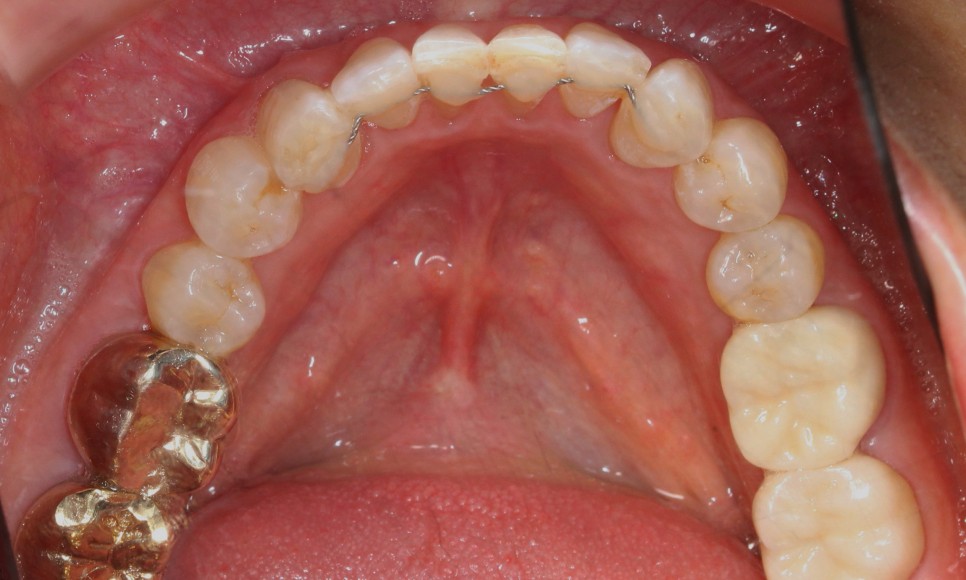

전체적인 아랫니의 치열도

심하게 삐뚤거렸던

처음의 모습과는 달리

아랫니 부분교정 (2D교정) 으로

이상적인 치아의 배열인

U자 곡선의 형태로

바뀌었습니다.